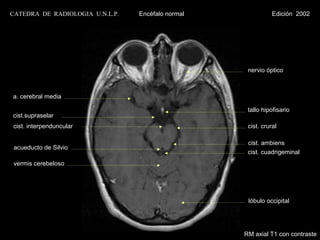

CATEDRA DE RADIOLOGIA U.N.L.P.   Encéfalo normal              Edición 2002

nervio óptico

a. cerebral media

tallo hipofisario

cist.supraselar

cist. interpenduncular                              cist. crural

cist. ambiens

acueducto de Silvio

cist. cuadrigeminal

vermis cerebeloso

lóbulo occipital

RM axial T1 con contraste